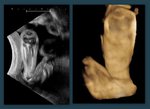

Fetal club hand deformity

This 2nd trimester fetus shows short forearm bone (radius) with radial deviation of the wrist. The image 1st (top left) is a B-mode ultrasound image showing this deformity of the hand. The other 3 images are 3-D (3 dimensional) ultrasound images showing the same anomaly in this fetus. These ultrasound images suggest  fetal radial club hand anomaly. Radial club hand is the commonest fetal club hand anomaly. It is important to look for other fetal malformations as this anomaly is usually not isolated. Ultrasound images courtesy of Dr. Dilraj Gandhi, India.

Reference: http://www.wheelessonline.com/ortho/radial_club_hand